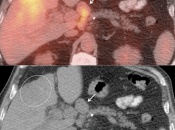

4. Abdomen & Pelvis

- The Heterogeneous Liver

- Liver Ablation

- Hypermetabolic Geographic Fatty Infiltration